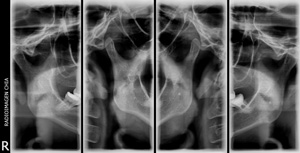

Radiografía extra oral donde vemos la articulación temporo mandibular en cuatro cortes, dos a boca abierta y dos a boca cerrada, en una sola placa.

¿Qué es la alteración de ATM?

La alteración de la articulación temporomandibular (ATM) ocurre cuando la bisagra que conecta el maxilar superior y la mandíbula inferior no trabaja correctamente. Esta bisagra es una de las articulaciones más complejas del cuerpo, es responsable de abrir y mover la mandíbula inferior hacia delante, atrás y de lado a lado. Todos los problemas que impiden el trabajo normal de este sistema complejo de músculos, ligamentos, discos y huesos, se agrupan bajo la denominación de alteración de ATM. Con frecuencia, la alteración de ATM se siente como si la mandíbula saltara o tronara o se atorara por unos segundos.